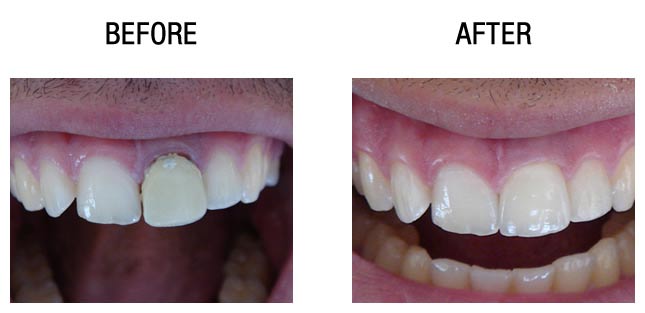

种植牙前后对比

种植牙前后对比